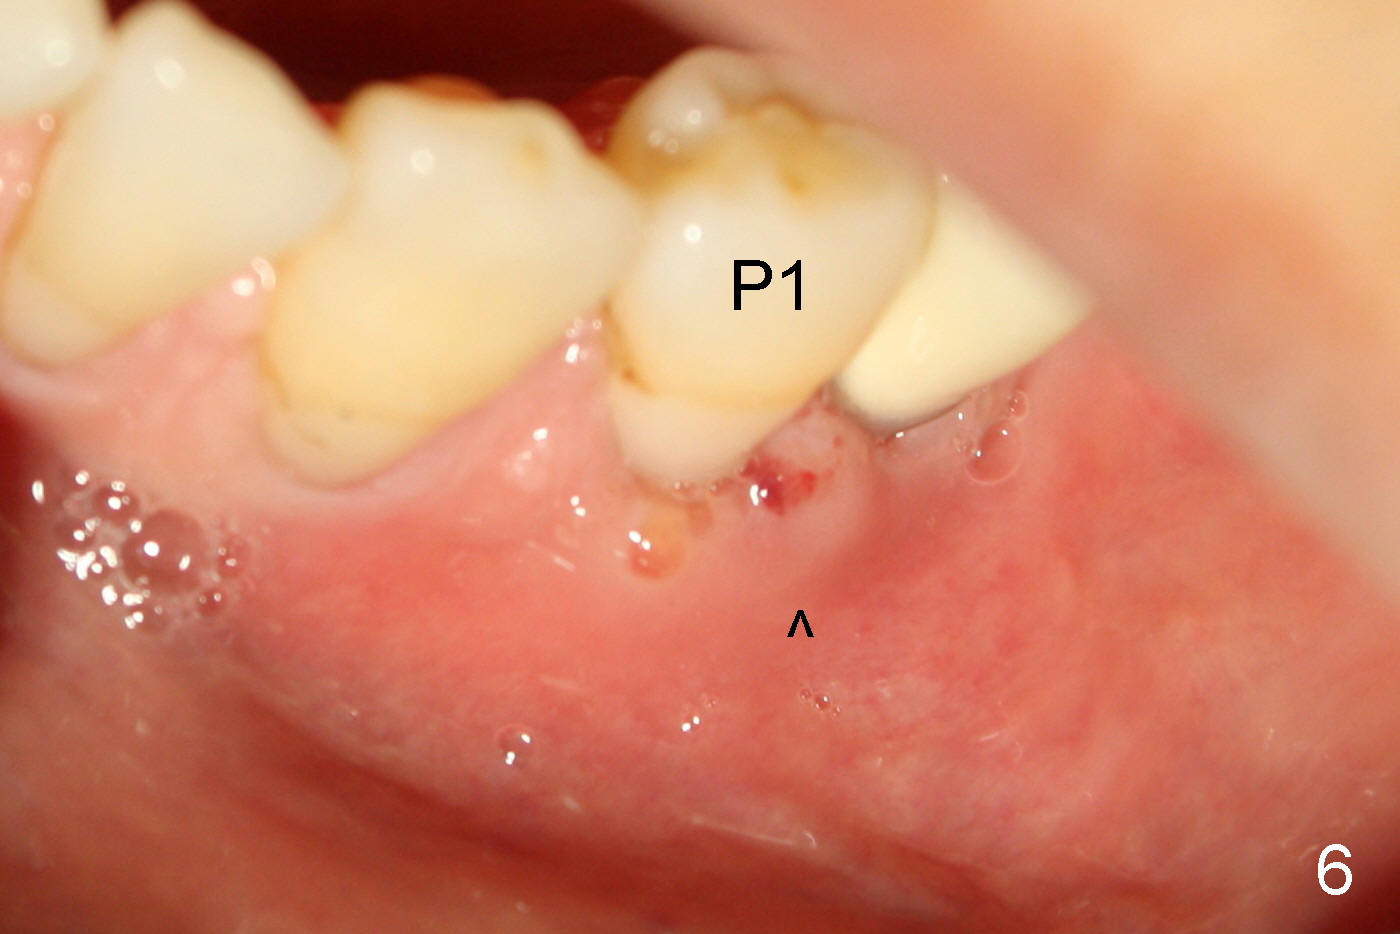

术后第三天病人因左下面部肿胀(图五),左下第一前臼齿(图六P1)远中颊侧牙龈肿痛(箭头),扣痛第一第二前臼齿差不多,牙髓活力测试第一前臼齿活髓。